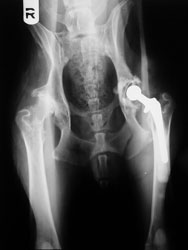

A 4-year-old male German shepherd suffering from severe hip dysplasia. He was treated with a total hip replacement.

A total hip replacement (THR) consists of replacing the acetabulum with a plastic cup, and the femoral head by a metal ball attached to a metal femoral stem. THR is often considered the Cadillac treatment, as it provides a pristine hip to a previously arthritic, pain-filled dog. For decades, the gold standard has been cemented systems. The dreaded complication is infection of the bone cement, or polymethyl-methacrylate, used to secure the implants.